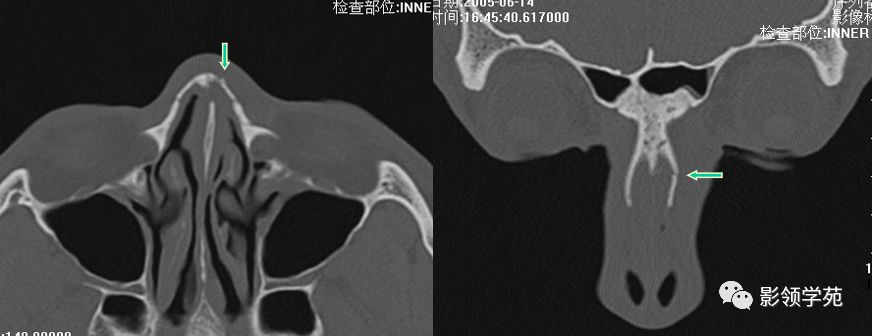

双侧鼻骨骨折

双侧上颌骨额突骨折

鼻中隔骨折

鼻颌缝

鼻骨间缝